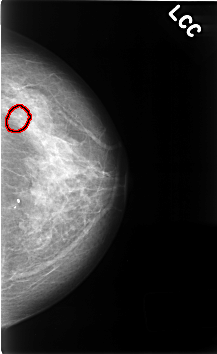

C_0466_1.LEFT_CC

LEFT_CC LINES 4600 PIXELS_PER_LINE 2816 BITS_PER_PIXEL 12 RESOLUTION 50 OVERLAY

FILE: C_0466_1.LEFT_CC.OVERLAY

TOTAL_ABNORMALITIES 1

ABNORMALITY 1

LESION_TYPE CALCIFICATION TYPE PLEOMORPHIC DISTRIBUTION CLUSTERED

ASSESSMENT 4

SUBTLETY 4

PATHOLOGY BENIGN

TOTAL_OUTLINES 1

BOUNDARY